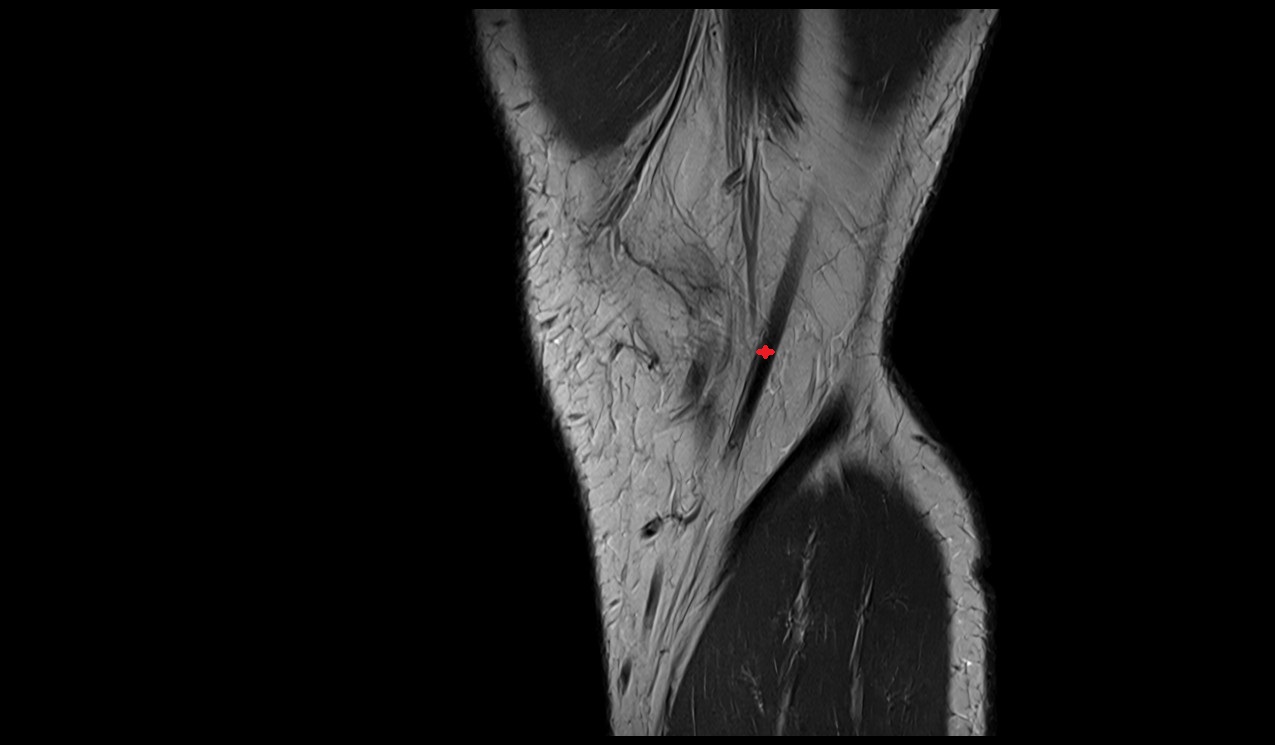

- Anterior cruciate ligament

- Posterior cruciate ligament

- Anterolateral ligament of knee